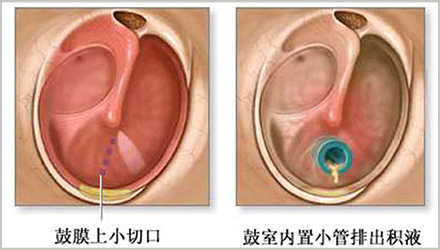

1. 中耳置管术

耳部炎症高发于儿童。根据美国耳鼻咽喉头颈外科学会的统计,孩子在5岁以前至少有过1次耳部炎症。 耳部炎症通常会自行消失且不会造成永久性损伤,但部分儿童患有慢性中耳炎,久而久之导致听力下降,学习成绩不佳,出现行为或言语障碍。

通常这种情况下,医生会建议通过手术,在耳内放置中耳管或压力平衡管,缓解中耳积液无法排出的情况下鼓膜增加的压力。

短期管通常在6至18个月内自行脱落,而长期管放置时间稍长并需要专业耳鼻喉科医生拔除。